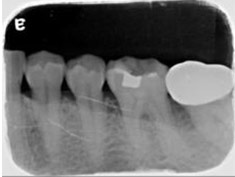

牙周初診時患者之口內觀。口內明顯牙菌斑及牙結石堆積。全口嚴重牙齦紅腫。治療前X光片。#37的近心側有較深的骨內缺損,剩餘齒槽骨高度只有20%。

A圖為#37根管治療完後的三個月放射線攝影根尖片。